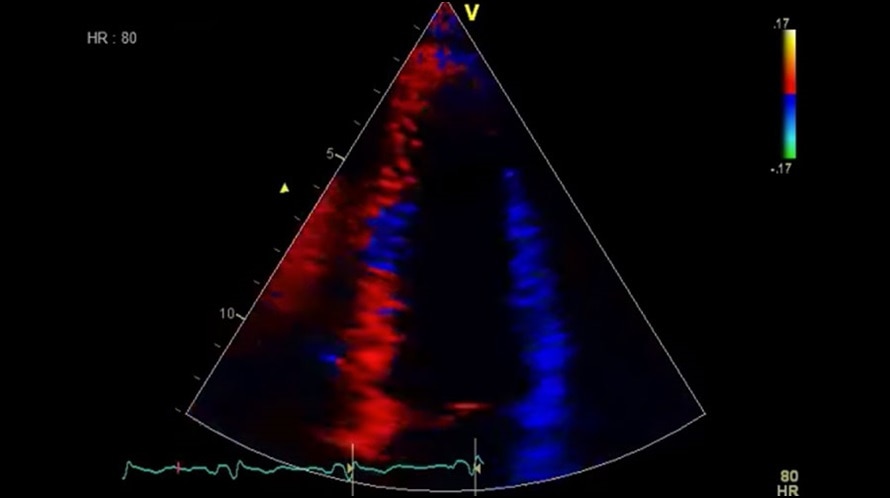

Режим цветового тканевого Доплера (TVI)

Отображает динамическую информацию от движущихся тканей сердца, позволяя с легкостью определять функцию левого желудочка.